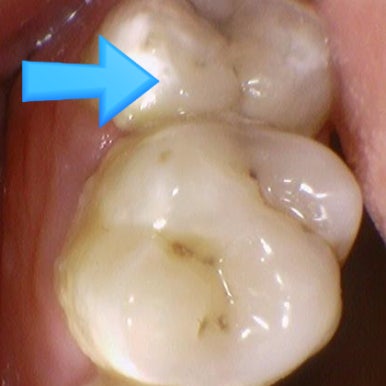

치아 사이 충치

특히 치아 사이 충치는 눈으로 하얗게 보인다고 방치했다가는

점점 치아 중간의 신경쪽으로 진행되어 신경치료를 하는 경우가 많으니

치료를 할 수 있을 때 빨리 치료를 하는게 좋습니다.